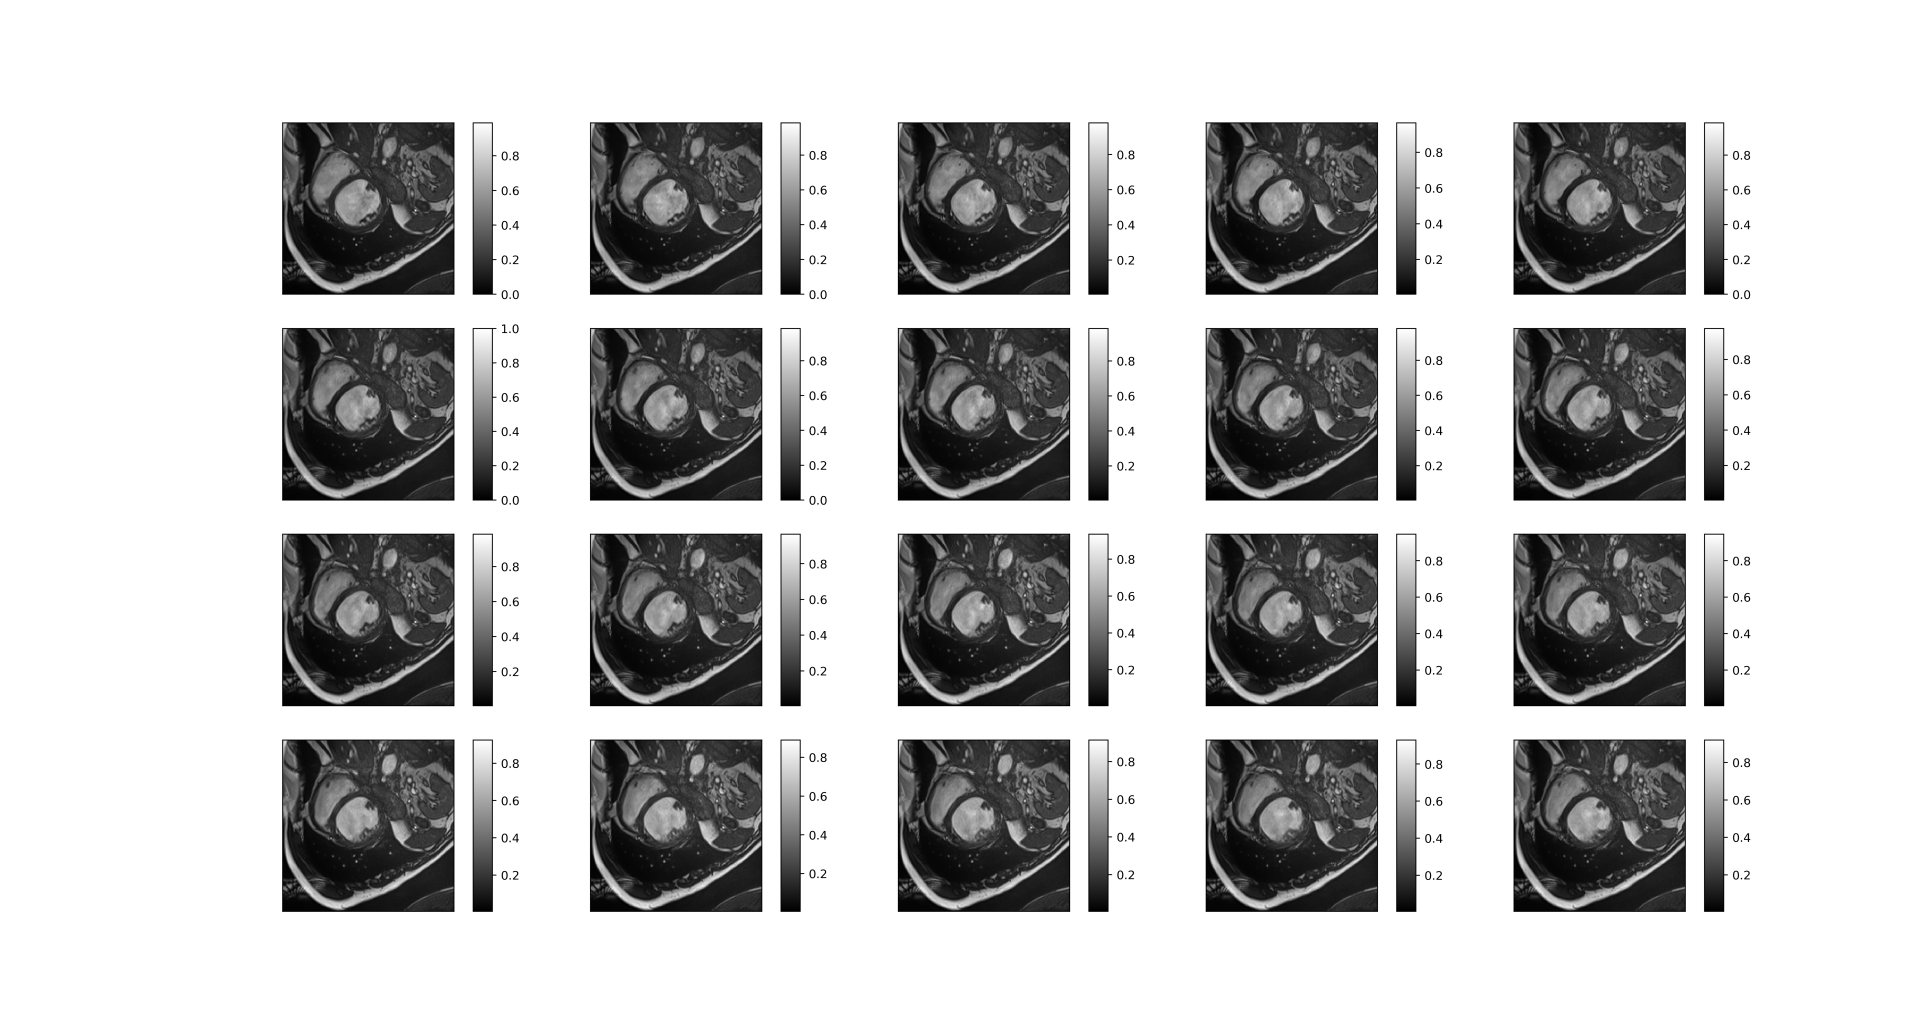

The aliased images(Graph 1.2) and fully sampled images (Graph 1.3) are as follows.

| Graph 1.2 Aliased images |

| Graph 1.3 fully sampled image |

A good reconstructed dynamic image is as follows:

| Before reconstruction |

|

| After reconstruction |

|

We can see that the reconstructed image is very clear with many details, though the upper right corner of the picture is slightly blurry.